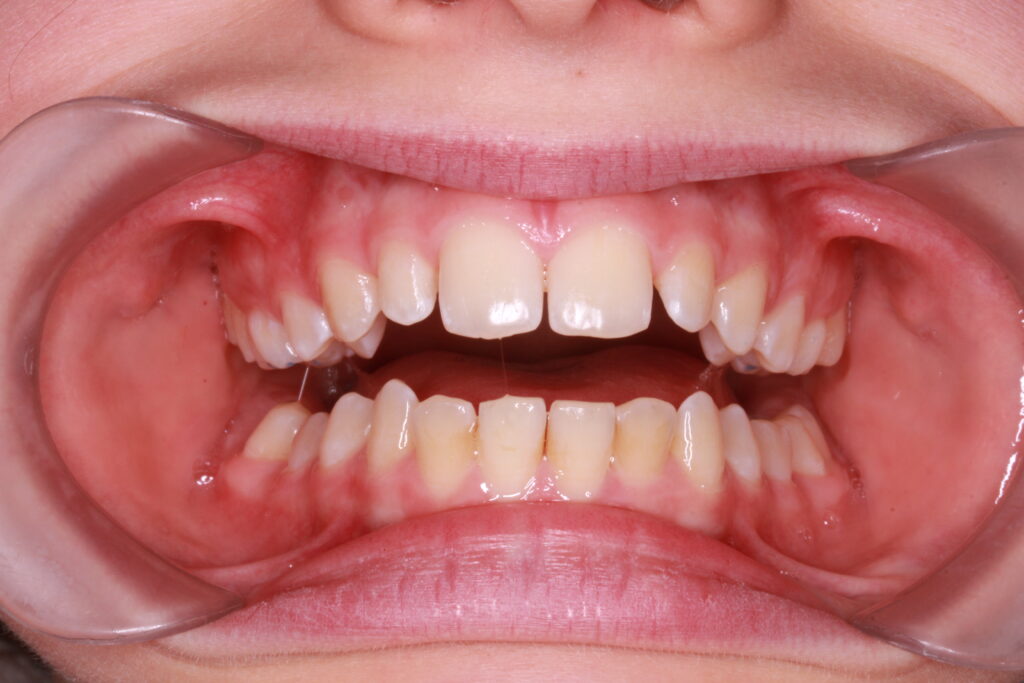

Az ALF készülék nem az agresszív erőhatásokra, hanem a funkcionális erők finom, biológiailag kíméletes irányítására épít. A klinikai tapasztalatok szerint ez tökéletes elég és mind a fogív fejlesztésében, keresztharapások megszűntetésében, helyteremtésben mind a nyelvtér növelésében jól működik.

A leggyakoribb a vegyes fogazat időszakában (6–11 év), de alkalmazható teljes tejfogazatban is nagyon korai kezelések esetében, akár 3-4 éves kortól is.